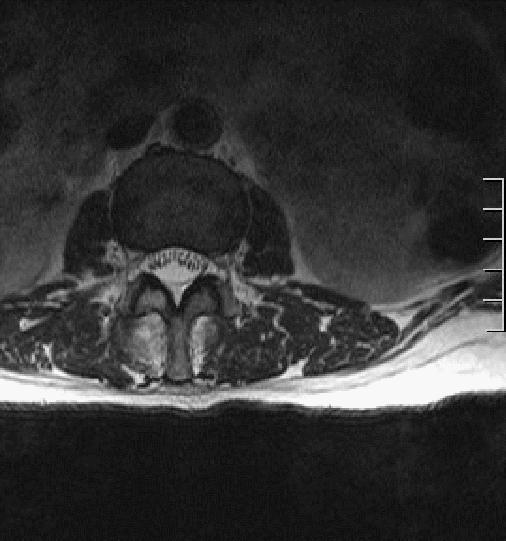

MRI增强

T1WI矢状位红色箭头所示腰2-3椎体附件区团块状异常信号,T1低信号为主,信号不均,T2WI高信号为主,其内见条形低信号分隔,压脂像明显高信号为主,向前突入椎管,临近蛛网膜下腔扩张呈三角形,相应水平椎管变窄,脊髓受压前移,信号增高,向后直达皮下脂肪层。轴位像椎体棘突、双侧椎弓根骨质破坏,见团块状软组织信号,病灶突入椎管内,相应水平椎管变窄,信号明显不均,其内见多发条形低信号,双侧竖脊肌受压移位。

黄色箭头所示蛛网膜下腔明显扩张, 病灶上下缘呈三角形扩张,脊髓受压信号增高,提示损伤。

绿色箭头可见腰4-5椎间盘髓核 T2 信号减低(注意其他椎间盘),提示间盘变性,纤维环后缘见点状T2及压脂像高信号,T1低信号,提示纤维环撕裂,需警惕椎间盘脱出可能。